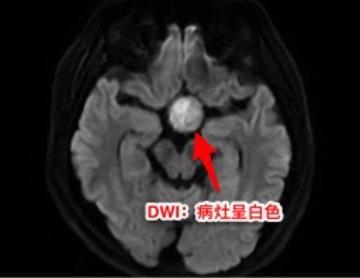

第一次经鼻手术后诊断为颅咽管瘤,可靠吗?27岁广西壮族自治区人,自幼视力不好。15个月前因多饮多尿、内分泌失调、视力下降在外院检查后诊断为颅咽管瘤,并作了经鼻内镜手术。取出一部分肿瘤内容物,病理报告为“角化物”。出院时诊断为“颅咽管瘤”。 一个月前患者又感视力下降,复查磁共振显示鞍区颅咽管瘤复发了,来找我作手术。头CT和磁共振见图。DWi显示肿瘤内容物呈白色,弥散受限,说明这不是颅咽管瘤。 手术中(我们采用开颅手术)看见肿瘤内容物为脱落角化上皮,其中未见毛发。将病灶囊皮及内